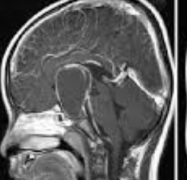

颅咽管瘤是一种来源于胚胎残余组织的良性肿瘤,颅咽管瘤约占儿童全部脑瘤的6%。任何年龄的人都有可能被诊断为颅咽管瘤,但在5到14岁之间较容易被诊...

颅咽管瘤 是起源于神经上皮的肿瘤,由鳞状细胞沿原颅咽管道长出。它们的发病率在每10万人年0.5至2.5之间,不因性别或种族而有所不同。颅咽管瘤占全部...

儿童颅咽管瘤是一种少见的、鞍区或鞍旁区胚胎性畸形的低级别组织学恶性肿瘤。由于颅咽管瘤与视交叉、脑垂体和下丘脑在解剖学上的邻近关系,其不良...

儿童期颅咽管瘤 是少见的,蝶鞍或鞍旁区域的胚胎发生畸形,伴有低度组织学恶性肿瘤。颅咽管瘤由于接近视交叉,脑垂体,经常影响儿童的生活质量(...

颅咽管瘤是由鞍区或鞍上区Rathke囊的残余细胞形成的肿瘤,具有囊性和实型成分。虽然它们是良性的,WHO为I级,但由于该病难以治愈,使得它们的生长行为...